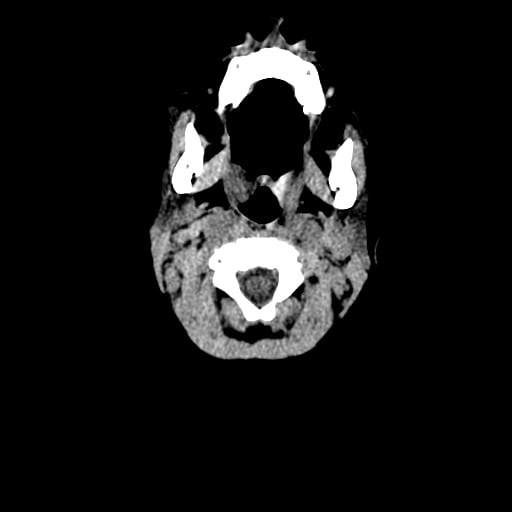

Age: 1

Sex: Male

Indication: Fall